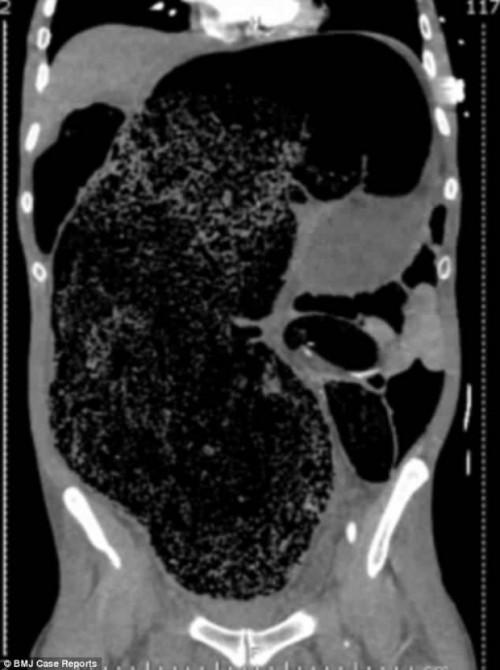

Ảnh chụp CT cho thấy lượng phân khổng lồ tích tụ trong khoang bụng bệnh nhân.

Theo chẩn đoán của các bác sĩ, khối lượng phân lớn tích tụ trong cơ thể này là nguyên nhân chính dẫn tới tình trạng đau đớn của bệnh nhân, bởi nó chèn ép các nội tạng xung quanh của người đàn ông như tăng áp lực lên dạ dày, làm tắc các mạch máu lưu thông xuống chân, làm tổn thương thận.